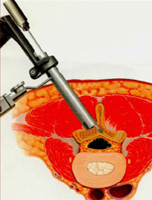

Como con las técnicas mínimamente invasivas hacemos unas heridas de menor tamaño en la piel nuestra capacidad para ver las distintas estructuras de la columna vertebral es menor por lo que necesitamos de técnicas auxiliares que nos ayuden a ver las zonas de la columna y poder trabajar con seguridad.

Estas técnicas auxiliares pueden ser el empleo de un escáner que mediante programas informáticos realizan una reconstrucción tridimensional de la columna (navegación vertebral), también se pueden emplear microscopios especiales que aumentan la visión de la zona; uso de tubos dilatadores que se colocan en la piel y nos permiten separar los músculos sin lesionarlos e introducir a través de ellos los instrumentales necesarios para la operación. (Fig 1 y 2)